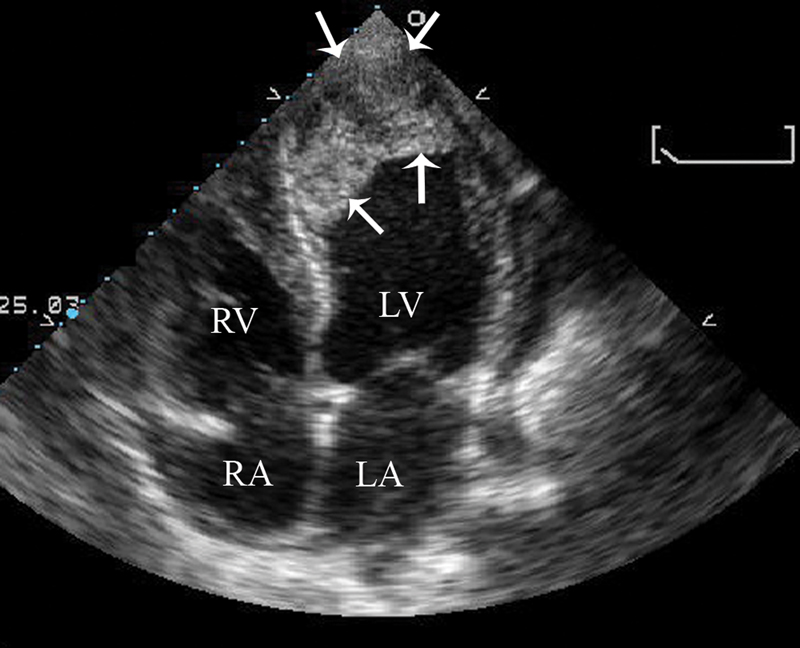

فحوصات تشخيصية لبعض امراض القلب والشرايين التاجية